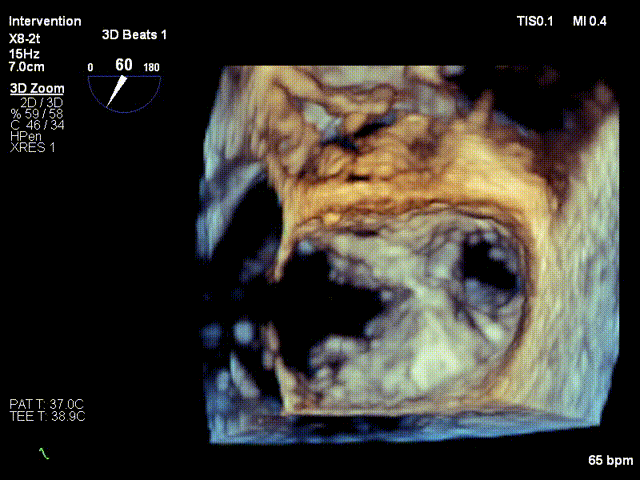

使用辅助系统置入第一枚XTW瓣膜夹后,手术团队经过多维度评估捕获效果,跨瓣压差1mmHg,前叶捕获14mm,后叶捕获8mm,双孔化良好,反流明显减少,肺静脉逆流明显减轻,不需再进行第二枚瓣膜夹的置入。释放瓣膜夹后,瓣膜夹稳定,手术顺利完成。手术最终通过仅置入一枚瓣膜夹即减轻了术前评估的两束反流,充分印证通过机器人操作的精准性优势,使患者二尖瓣治疗的效果获得更进一步突破。

术后TEE影像